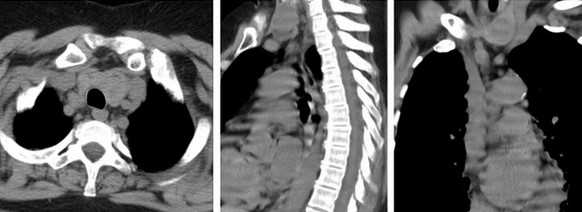

КТ без контраста у пациента с интерстициальным заболеванием легких в анамнезе и трансплантацией правого легкого показывает суженный участок анастомоза правого бронха (красная стрелка). Собственное левое легкое уменьшено в размерах, с признаками бронхоэктазов, бронхиолоэктазов (черная стрелка). Сужение центрального дыхательного пути на выдохе у трансплантированного легкого (синяя стрелка).

КТ средостения, аксиальная, сагиттальная и фронтальная проекции